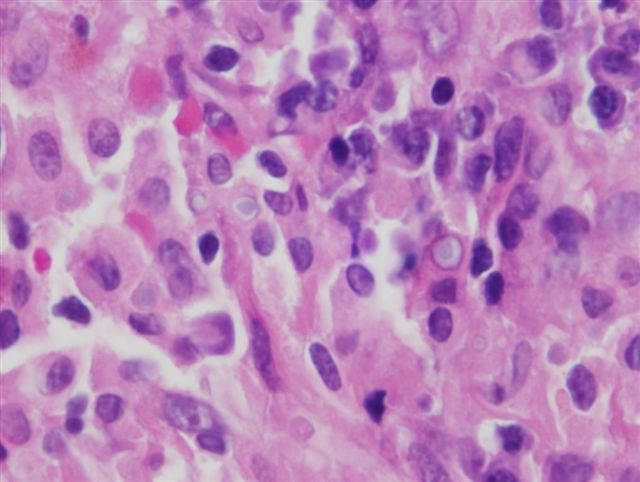

List three risk factors for developing this lesion.

Cystitis glandularis

Urachal remnant

Exstrophy

(Adenocarcinoma - look for pleiomorphic cells lining glands)